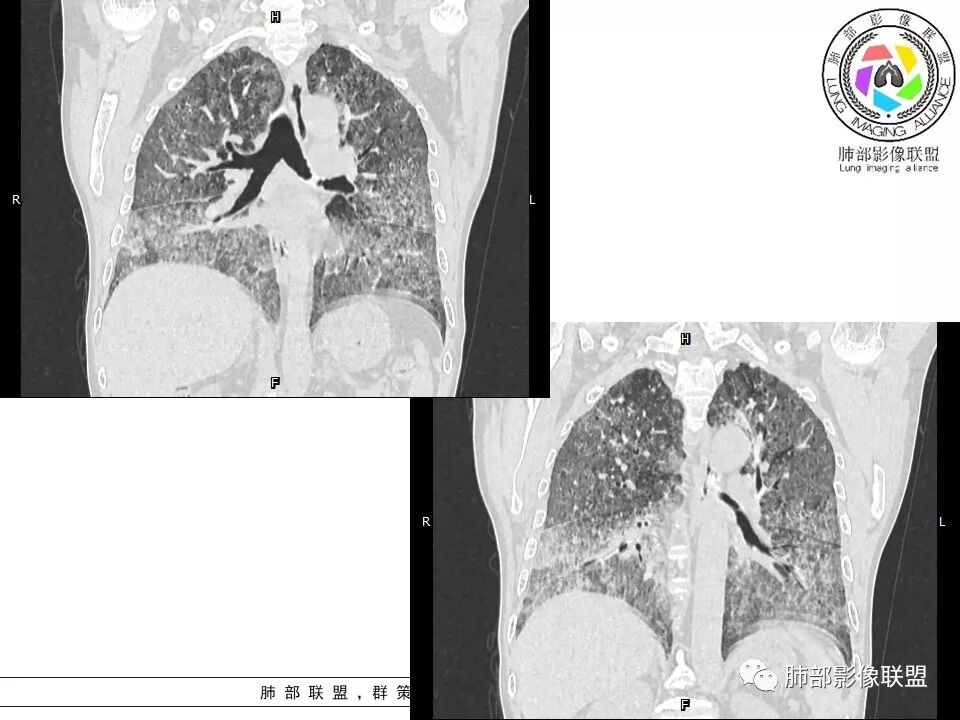

徐婕:双肺弥漫磨玻璃,铺路石,部分斑片实变。病程一年,血白细胞增高,考虑肺泡蛋白,合并双肺感染?鉴别腺癌

八爪:弥漫分布磨玻璃密度影,小叶间隔增厚,典型铺路石征,考虑PAP伴发感染性病变,鉴别特发性间质性肺炎,弥漫性腺癌,建议支气管灌洗;左肺上叶舌段不规则团片状阴影,显示不清,密切随访

笨丫头:双肺弥漫磨玻璃影,间质性改变,既往有煤炭工作史,考虑尘肺,左肺占位,边界不清,不除外合并肿瘤,腺癌?

老陈:小叶间隔明显增厚,CEA升高,肺癌,淋巴管炎。

小谢:慢性病程,无发热,双肺弥漫性病变,GGO,铺路石征,首先考虑PAP,鉴别肺腺癌

一米阳光:中老年男性,病程长。双肺弥漫性ggo,小叶间隔明显增厚,铺路石样改变,考虑PAP,鉴别pcp。建议支气管镜检查并灌洗。病史有尘肺接触史,排除尘肺合并结核

我心飞翔:中年男性,双肺弥漫磨玻璃影,铺路石征,病灶内可见扩张支气管,CEA高,血象高,黄痰,考虑PAP并感染,腺癌待排

郑氏刀刀:双肺弥漫性磨玻璃影,伴铺路石征,下叶为主,且见斑片实变影,白细胞高,结合执业史,尘肺,PAP伴感染,腺癌待排。

小景:双肺弥漫磨玻璃影,小叶间隔增厚,呈碎石路征。患者粉尘接触史,考虑PAP。左肺舌段病灶,抗感染无吸收,腺癌待排。

上肺为主小叶中心型肺气肿——吸烟

碎石路征,下肺为主

肺部结节

左上叶斑片状高密度影

肺血坠积

南边:只有GGO+网格(小叶间隔增厚),然后就是分布的问题

PAP的影像特点:

1、GGO+网格——碎石路征

2、分布无特定位置,较随机

3、可有少许实变——部分与层厚有关

4、小叶间隔内静脉增粗

5、病灶较多时部分可见重力趋势

6、很少有纤维化改变